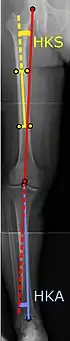

![]() |

Ángulos comúnmente medidos antes de la cirugía de reemplazo de rodilla: |

Para indicar el reemplazo de rodilla en caso de osteoartritis, su clasificación radiográfica y la gravedad de los síntomas deben ser sustanciales. Dicha radiografía debe consistir en radiografías en carga de ambas rodillas: AP, lateral y 30 grados de flexión. Es posible que las proyecciones AP y lateral no muestren un estrechamiento del espacio articular, pero la vista en flexión de 30 grados es más sensible al estrechamiento. También se utilizan proyecciones de longitud completa para ajustar la prótesis para proporcionar un ángulo neutro para la extremidad inferior distal. Dos ángulos utilizados para este propósito son:

- Ángulo cadera-rodilla-eje (CRE),[8] un ángulo formado entre una línea que pasa por el eje longitudinal de la diáfisis femoral y su eje mecánico, que es una línea desde el centro de la cabeza femoral hasta la muesca intercondilar de la diáfisis femoral. fémur.[10]

- Ángulo cadera-rodilla-tobillo (CRT),[9] que es un ángulo entre el eje mecánico femoral y el centro de la articulación del tobillo.[10] Normalmente se encuentra entre 1.0° y 1.5° de varo en adultos.[11]